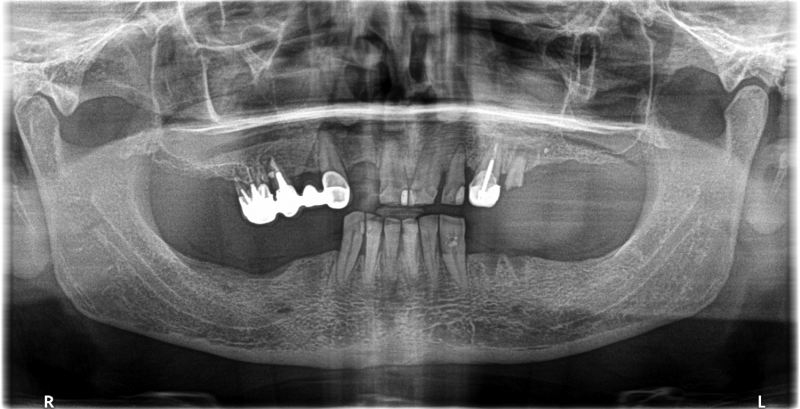

Wykonana praca protetyczna:

- most pełnołukowy na czterech implantach

- mosty pełnoceramiczne na implantach w łuku dolnym

- odbudowa flow-injection na zębach przednich dolnych

Praca wykonana przez: dr n. med. Michała Kubiszyna, lek. dent. Annę Andrzejewicz-Melaniuk

Leczenie zachowawcze: Lek. dent. Paweł Kruk